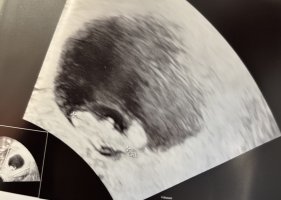

Pga risikosvangerskap skal jeg følges tett opp, og fikk derfor uventet en ultralyd i dag også for å bekrefte liv før mølla settes i gang. 8+1 (mensdato 8+5) og hun klarte faktisk å ta utvendig ultralyd (new achievement unlocked). Lille ble nå målt til ca 8+2

Og på de 8 dagene har lille vokst nesten 1 cm!

Ca 1,76-1,78 cm